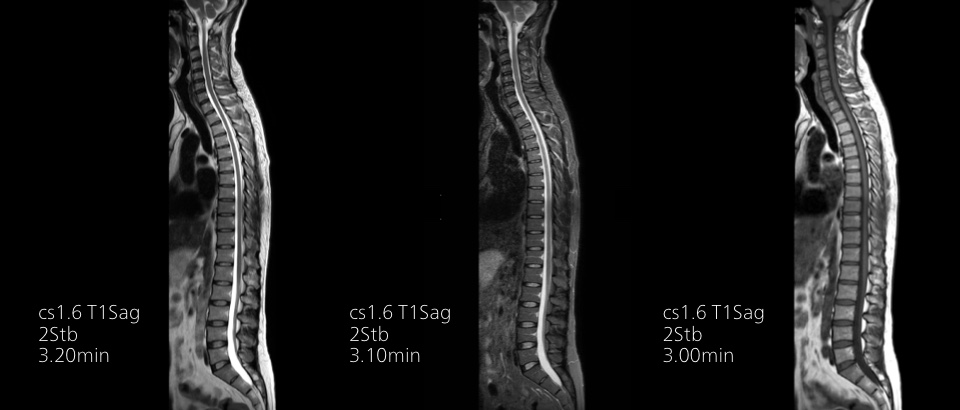

Compressed SENSEは、実質的に同等の画質を保ちつつ、撮像時間を最大50%²高速化します。

時間を味方につける - Compressed SENSEを使用すると、実質的に同等の画質を保ちつつ、撮像時間を最大50%²短縮できます。空間分解能が60%向上した高品質のMR画像を得ることで確実な診断が可能になります。